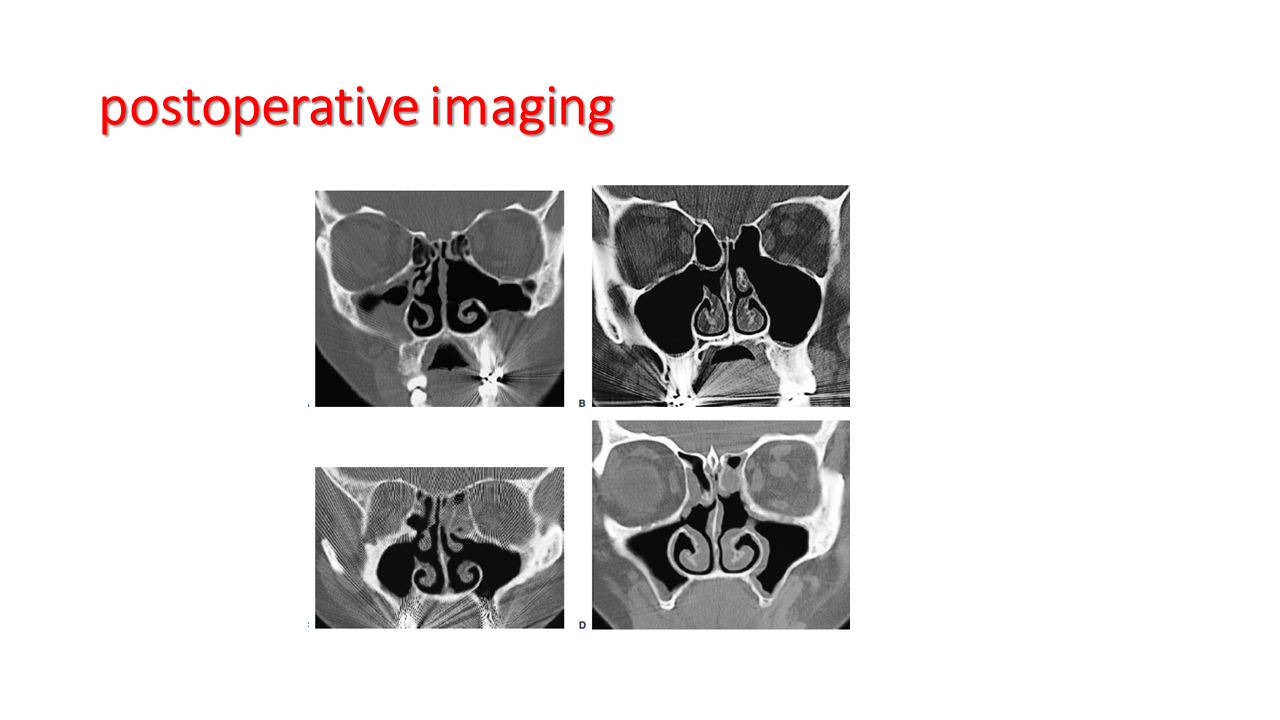

FESS Case Review and Radiologic Analysis (30.09.2016)

Case-based presentation focused on pre- and postoperative imaging in functional endoscopic sinus surgery (FESS). Includes anatomical landmarks, surgical variations, sinus pathology, and technique evaluation. Delivered by Dr. Levon Galstyan at AAOMFS.